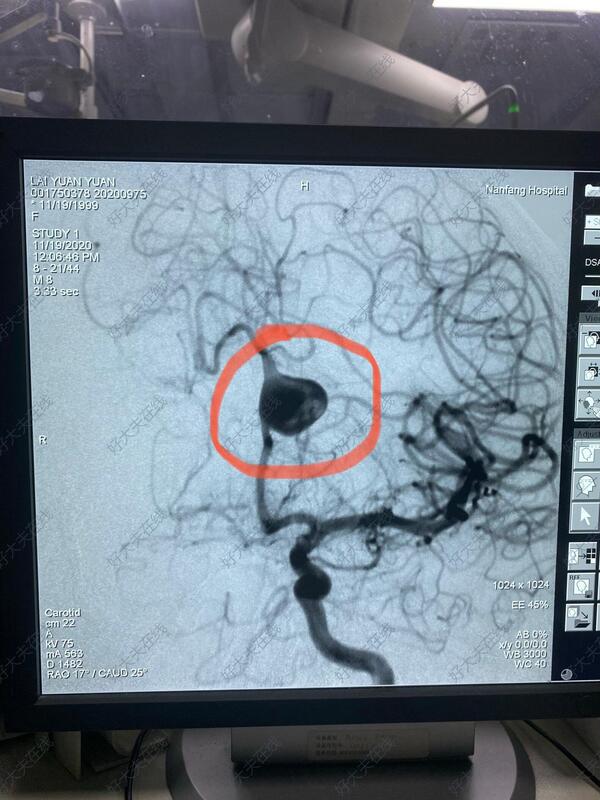

治疗前

21岁年轻女性,头痛检查发现左侧大脑前动脉A2段大型动脉瘤,植入密网支架重建血流,以达到修复血管,治愈动脉瘤的目的